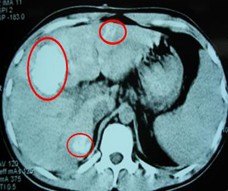

患者情况:肝细胞性肝癌,术后复发,右肝内多个病灶。治疗方案:瘤内注射今又生1×1012VP/次/周,共8周,同时联合肝动脉化疗栓塞(TACE),1次/月,共2次。下图示:左侧上下两图为治疗前,CT示血管丰富;右侧上下两图为治疗一个疗程后,碘油均匀沉积,肿瘤血供减少。

治疗前

治疗后